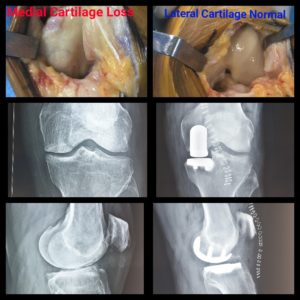

History: 85-yr-old patient on whom Partial Knee Replacement was performed by Dr. Amyn Rajani

Case: A lot of patients and doctors ask Dr. Amyn Rajani why Partial Knee Replacement instead of Total Knee Replacement for elderly. Look at the lateral cartilage of the 85-yr-old operated patient. It’s absolutely pristine then why replace it then. Also when at this age recovery from Total Knee Replacement would take time, results of Partial Knee Replacement are extraordinary. A lot of people had advised this patient a TKR looking at his age, Dr. Rajani felt that you don’t need to look at the age and pathology. Doctor performed a successful Partial Knee Replacement Surgery/ Unicondylar Knee Replacement on the patient the other day and he walked next day and today patient is pain- free and will be discharged in a day’s time.